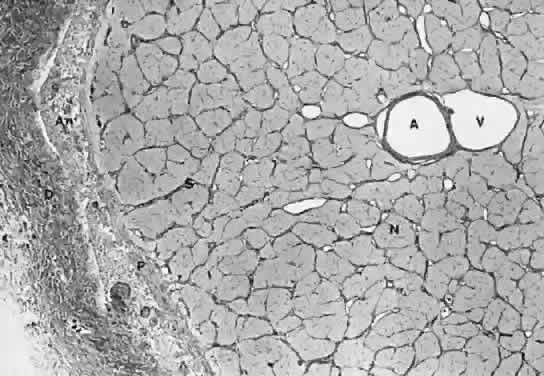

The intraorbital portion of the optic nerve is enclosed by three sheaths that are continuous with the meninges of the CNS: the dura mater, arachnoid, and pia mater (Fig. 6). The outermost of these is the dura mater, a dense collagenous and elastic tissue. Anteriorly, the dura mater frays and inserts into the sclera and rectus muscle sheaths along with the ciliary arteries and nerves. Posteriorly, the dura mater divides into two layers. One of these layers fuses with the periosteum of the bony canal and with Zinn's annulus at the apex of the orbit; the remaining layer is tightly adherent to the bone of the canal and the optic nerve. When the optic nerve passes the cranial foramen of the canal, the dura mater becomes the periosteum of the sphenoid bone. Therefore, even small lesions that occur within the canal or at its openings will compress and damage the optic nerve.

Fig. 6. Cross-section of the optic nerve. (A) central retinal artery; (V) central retinal vein; (S) connective septa from the pia mater; (P) pia mater; (An) arachnoid cell nests; (D) dura mater; (N) axon bundles intermingled with glia cell nuclei.

The arachnoid is composed of trabeculae of collagenous and elastic fibers lined by meningothelia. It contains numerous vessels, along with some fibroblasts and histiocytes. The meningothelia often proliferate in a concentric pattern and form onion-like structures, with or without calcification, known as the psammoma bodies or corpora arenacea, respectively.

The pia mater lies tightly on the surface of the nerve and consists of collagenous fibers, elastic fibers, and a fused glial layer. The pia mater invests the nerve and sends fibers into it to form the characteristic septa. The septa are separated from the surrounding nervous tissue by the foot processes of the astrocytes, but they are continuous with the collagenous adventitial sheaths of the central retinal artery and vein within the optic nerve. The pia mater joins the sclera and choroid anteriorly; posteriorly, it continues through the optic foramen to form the single sheath around the intracranial portion of the optic nerve.